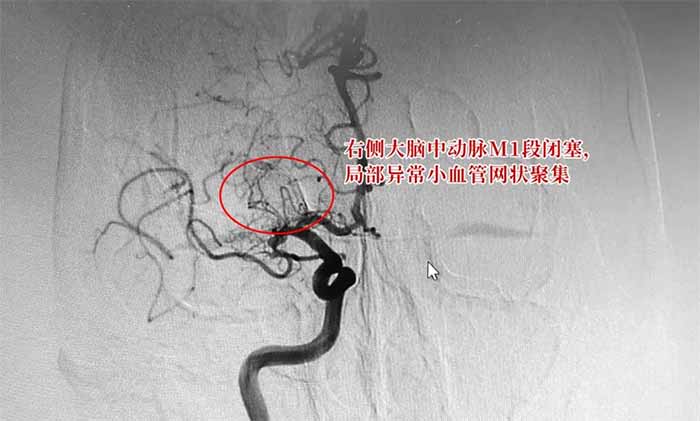

▲ 烟雾病DSA检查影像

烟雾病是一种慢性闭塞性脑血管疾病,以双侧颈内动脉末端和(或)大脑前动脉、大脑中动脉起始部缓慢进展性狭窄以致闭塞,出现代偿性异常血管网为特点,因其异常血管网在脑血管造影时似“烟雾缭绕”,故称为“烟雾病”。